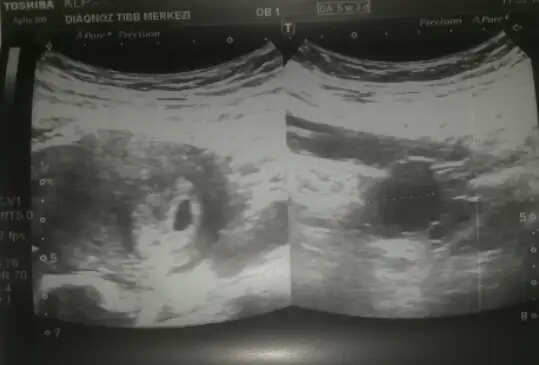

X-ray cihazının kanıtlanmış bir zararı yok gebelikte. Ben kalp atısını bekliyorum. Duyunca söyleyecegim. Yaklasık 8 haftalık olacak o zamana.kızlar çevrenize ne zaman söyleyeceksiniz..